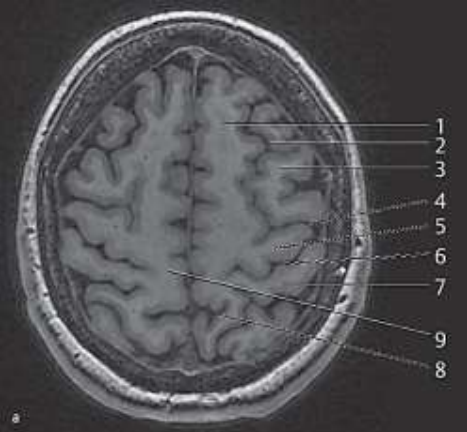

Paciente do sexo feminino, 33 anos, obesa, apresentando queixa de turvação visual progressiva e cefaleia de difícil tratamento. Foi avaliada por oftalmologista que descreve edema de papila. Realizou RM de crânio com os achados abaixo.

Assinale a alternativa que corresponde ao provável diagnóstico para o caso acima

Com base na imagem de ressonância magnética a seguir e seus conhecimentos de neuroanatomia radiológica, assinale a alternativa que descreve corretamente o nome e a função da estrutura indicada pelo número 5